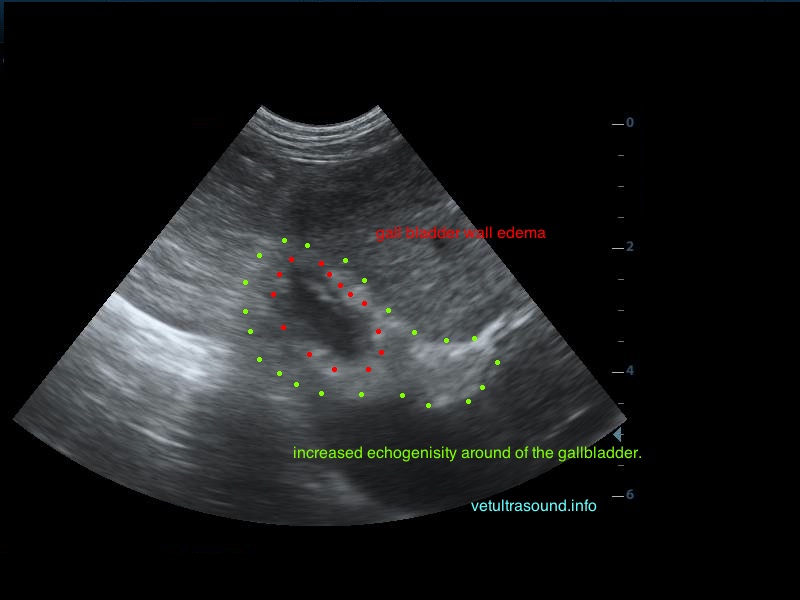

Ήπια ηπατομεγαλία με αύξηση της ηχογένειας του οργάνου, χωρίς παρουσία εστιακών αλλοιώσεων(pic.4). Πάχυνση του τοιχώματος της χοληδόχου κύστης με εικόνα βλεννοκήλης ( kiwi sign) και έντονη υπερηχογένεια στη περιοχή περί αυτού(pic.1&2). Ήπια διάταση της νεφρικής πυέλου, πιθανόν λόγω της πολυουρίας και πολυδιψίας(pic.3). Επασβέστωση στον οπίσθιο πόλο του δεξιού επινεφριδίου και αύξηση των διαστάσεών του(pic.6). Απουσία ασκιτικής συλλογής και παθολογικά διογκωμένων λεμφαδένων.

Η διάγνωση μετά τον υπέρηχο τέθηκε ως βλεννοκήλη της χοληδόχου κύστης με εικόνα χολοκυστίτιδας σε υπόβαθρο πιθανού υπερφλοιοεπινεφριδισμού. Θα πρέπει να γίνει επιβεβαίωση με αιματολογικές εξετάσεις του υπερφλοιοεπινεφριδισμού, καθώς η βλεννοκήλη της χοληδόχου κύστης είναι μία από τις επιπλοκές αυτού.